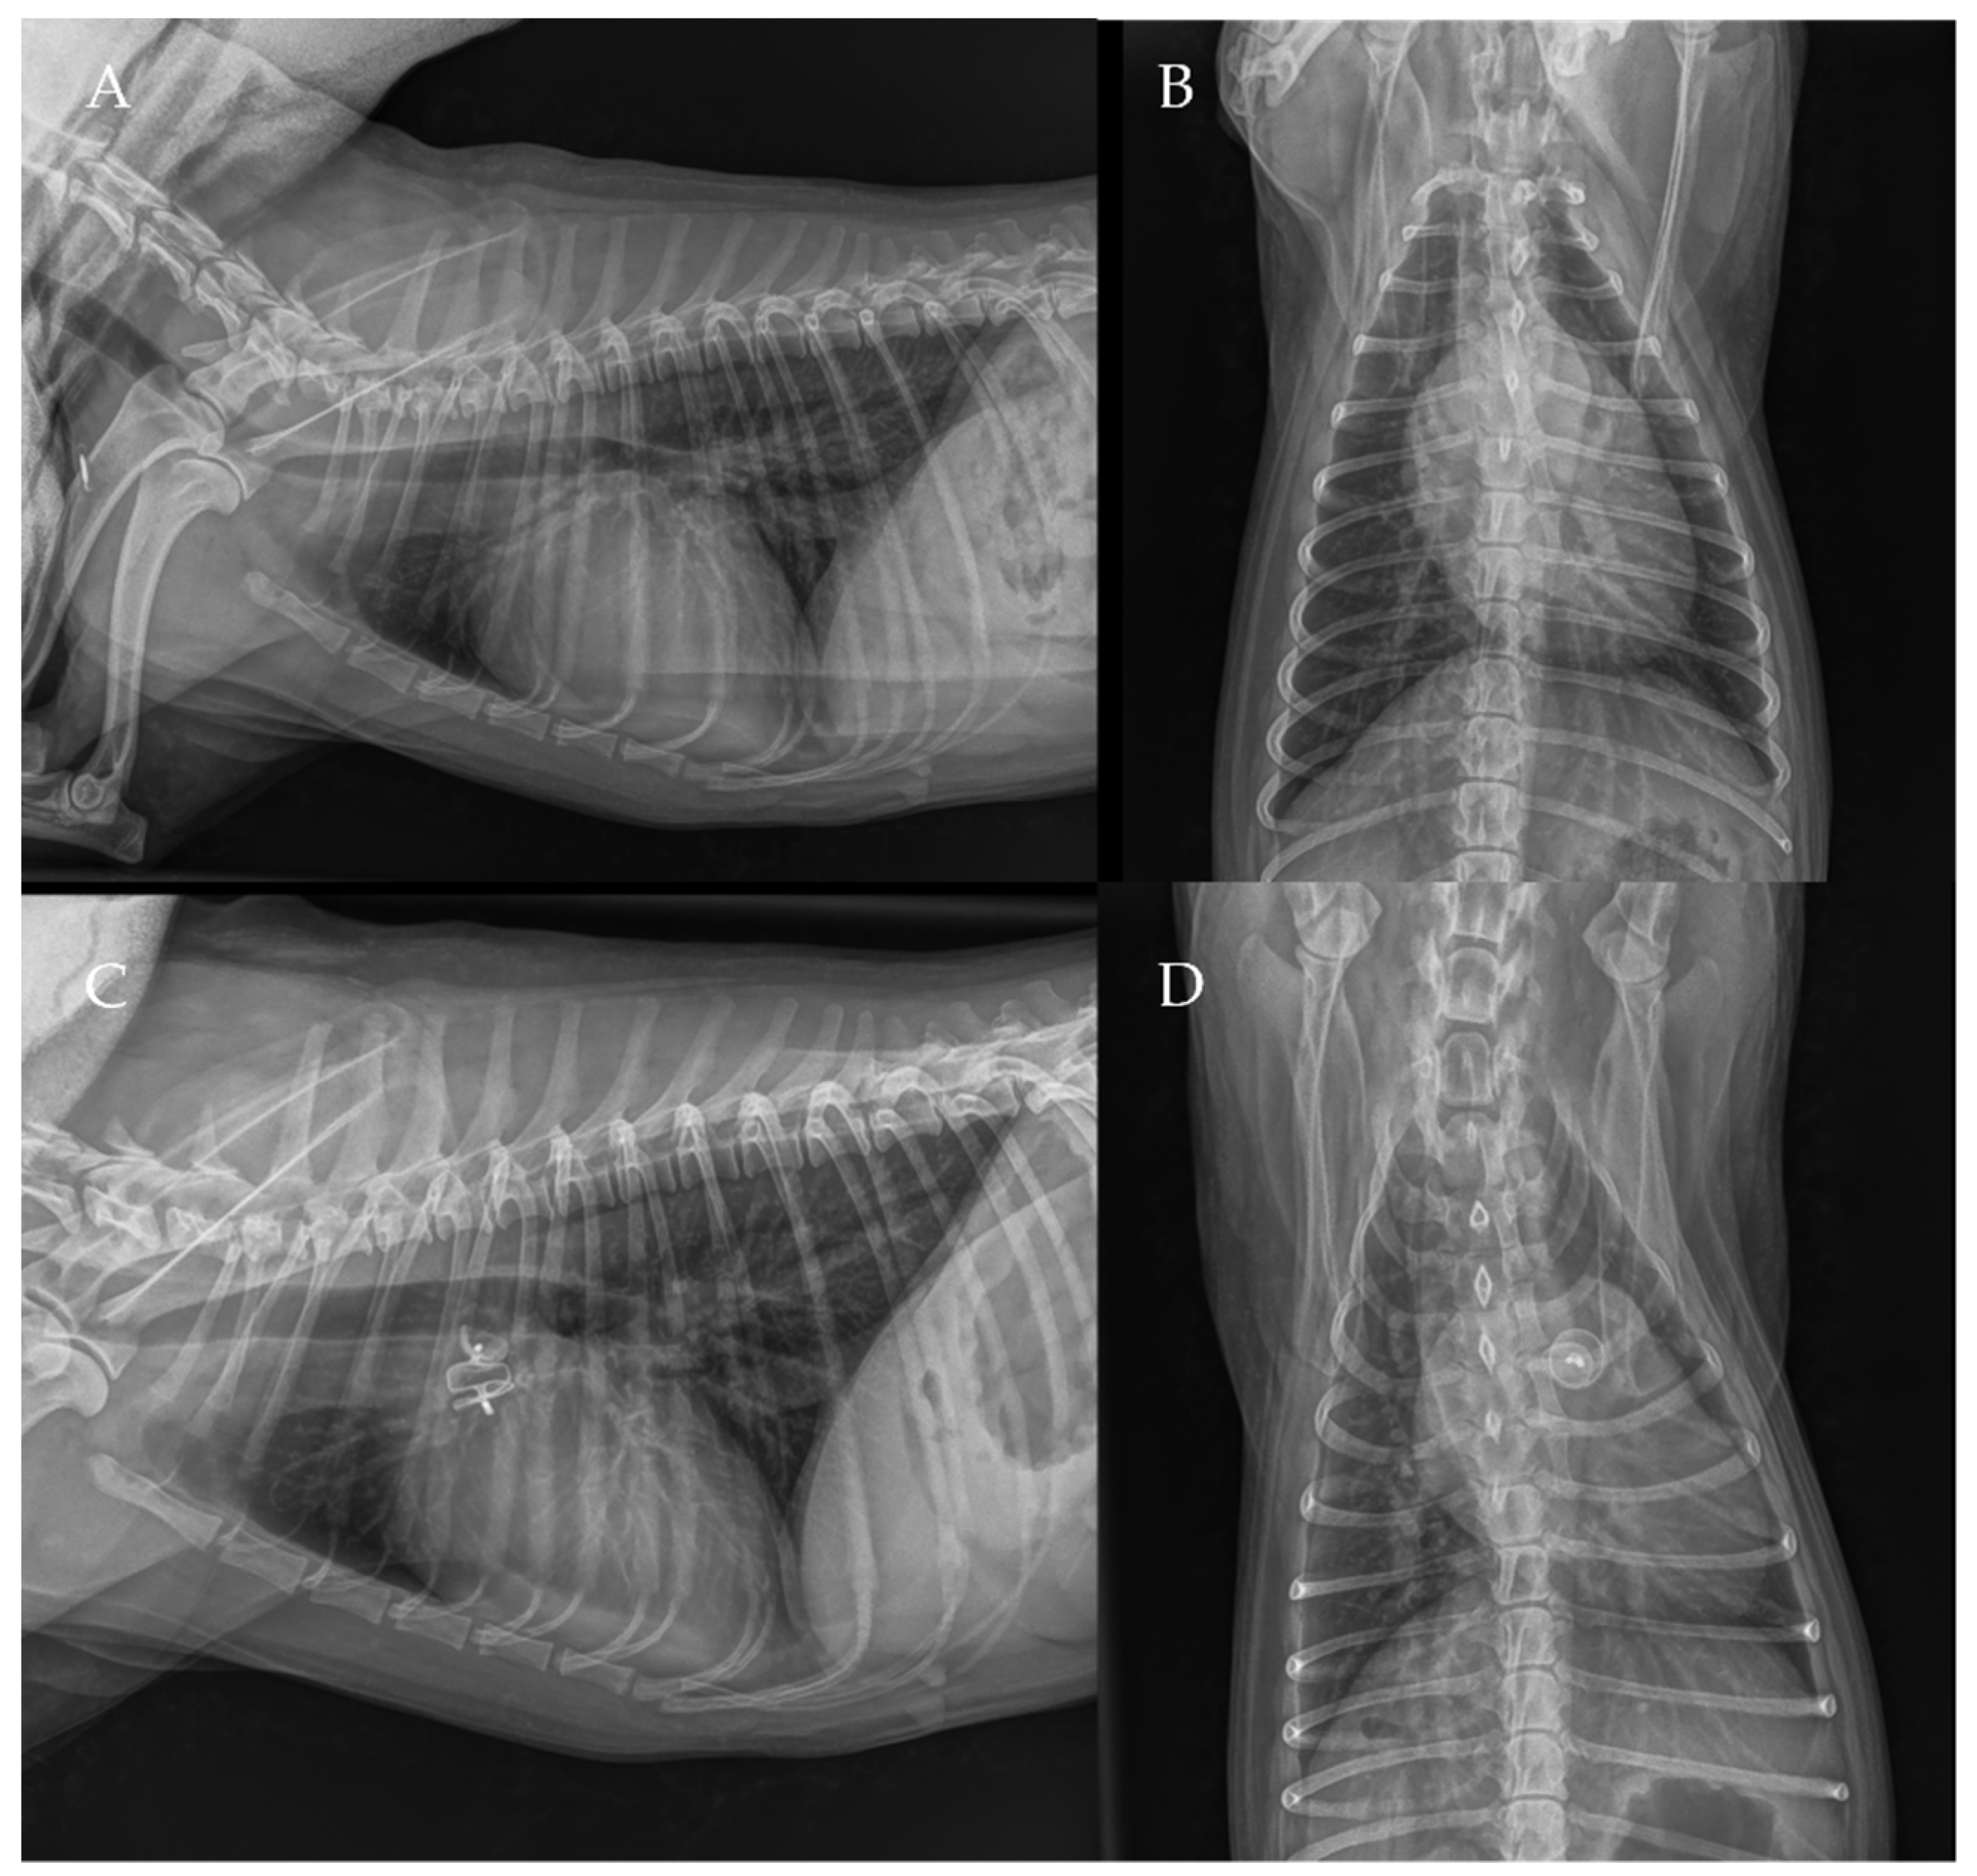

The thoracic radiographs performed before and just after the procedure showed a reduction in the cardiac silhouette as well as significant reduction of the over-circulation vascular pattern for all dogs (Figure 8, Figure 9, Figure 10, Figure 11 and Figure 12).

Figure 8. Pre-procedure (A,B) and post-procedure (C,D) left lateral and dorso-ventral thoracic radiographs of Case 1. L: left; R: right.